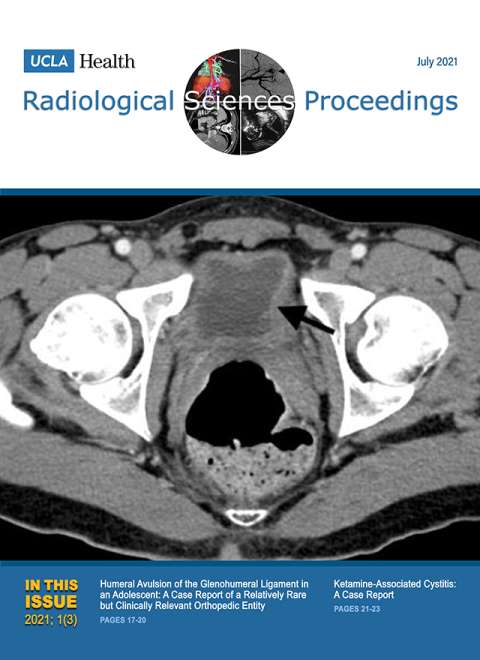

January 2021

Volume 1, Issue 1

- Giant Hepatic Regenerative Nodule in a 17-year-old with Alagille Syndrome

- Closed Sagittal Band Injury: A Case Report.

October 2021

Volume 1, Issue 4

- Electronic Integrated Diagnostic Report for Presenting Results of Breast Imaging and Breast Biopsy

- Iatrogenic Axillary Pseudoaneurysm Caused by Ultrasound-guided, Vacuum-assisted Biopsy of the Axillary Lymph Node: A Case Report

- Emergency Intravascular Aortic and Iliac Artery Lithotripsy to Facilitate Thoracic Endovascular Aortic Repair of a Ruptured Thoracic Aortic Aneurysm: A Case Report

- Acute Large Bowel Obstruction due to Pelvic Endometriosis: A Case Report